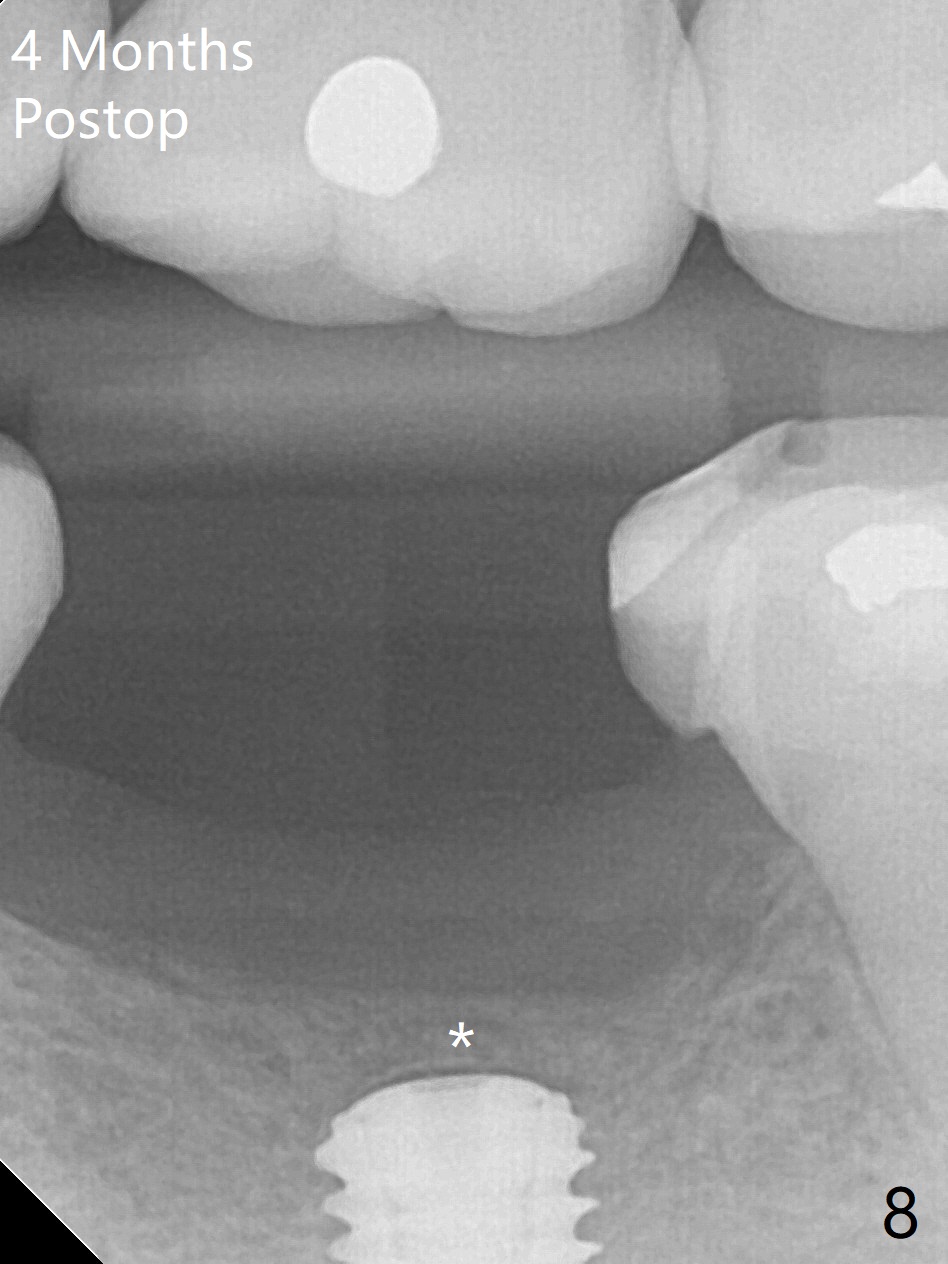

CT taken 4-5 months post extraction shows the outline of the socket at #19 (Fig.1 pink and red dashed line). By the time of surgery (6-7 months post extraction), the ridge looks narrow (Fig.2). In fact the socket does not heal (Fig.3). Osteotomy starts at the mesial border of the socket (Fig.4). When a 5x10 mm dummy implant is placed, the axis begins to be tilted distally (Fig.5 red line), which is more obvious when a definitive longer implant (5x11.5 mm) is placed (Fig.6,7). Osteotomy (Fig.1 arrow) at the mesial slope of the socket (red dashed line) should be initiated more mesial to compensate for the distal drifting while osteotomy is being increased and the implant is being placed. The distal defect is filled with Vanilla graft. Probably due to the mesial slope and the distal defect, the primary stability is <10 Ncm. A healing screw is placed with Vanilla allograft/autogenous bone. The bone forms coronal to the implant 4 months postop (Fig.8 *), which is removed for uncover. The mesial gingival embrasure of the permanent crown is large (Fig.9 *), as related to the mesial undercut associated with a 5.7x4 mm A 15 degree angled abutment (Fig.10). Reduction in the undercut should be able to help lab decrease the gingival embrasure (Fig.11 red line). The bone density around the implant increases with distinct trabecular pattern consistent with stress 5 months post cementation (1 year postop, Fig.12).